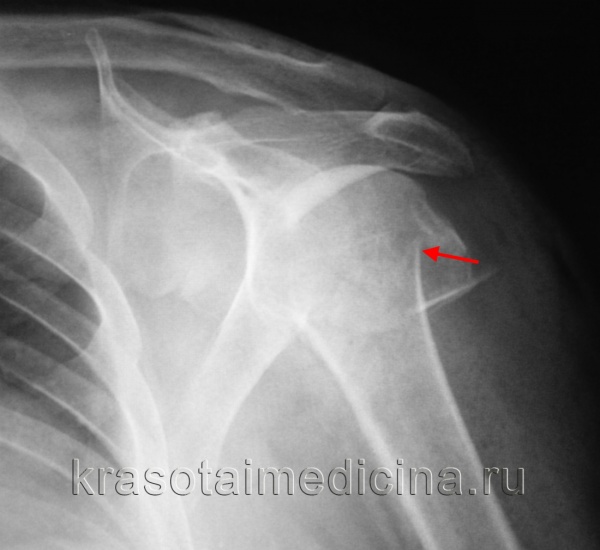

(Слева) На передне-задней рентгенограмме определяется перелом хирургической шейки. Сложно сказать, является ли медиальный край головки плечевой кости отдельным отломком перелома или остеофитом.

(Справа) На 3D КГ с реконструкцией у этого же пациента определяется перелом хирургической шейки и подтверждается, что медиальный край является большим остеофитом.